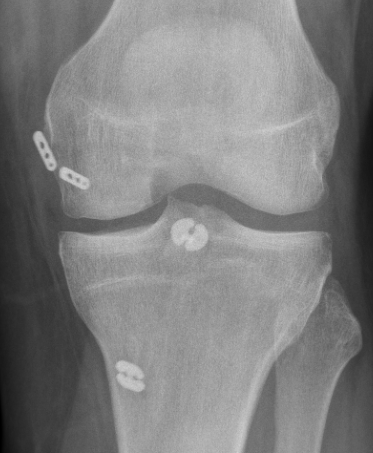

Acute femoral peel off of PCL

Acute Surgical Options

1. Repair bony avulsion

2. Acute suture repair of femoral peel off +/- augmentation

Acute repair of femoral peel off with suture tape augmentation

Indication

Femoral avulsion of the PCL

Acute injury

Technique

Repair to PCL to femoral insertion with sutures

Pass suture tape through tibial insertion to femoral insertion PCL to augment